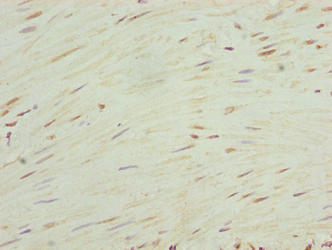

Immunohistochemistry of paraffin-embedded human colon cancer using CSB-PA867192LA01HU at dilution of 1:100

Immunohistochemistry of paraffin-embedded human small intestine tissue using CSB-PA867192LA01HU at dilution of 1:100